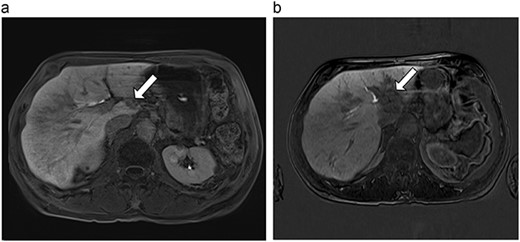

| 4 (6a,b) | 51, M | Colon adenocarcinoma | 6 cycles FOLFOX | 4 | Laparoscopic microwave ablation | 14 | 23.8 | 9.8 | 13 | Yes |

(a) Pre-ablation MRI demonstrating 14 mm lesion in caudate lobe of liver. (b) Post-ablation MRI (23 days postoperatively) demonstrating 23.8 mm complete ablation of caudate lesion.